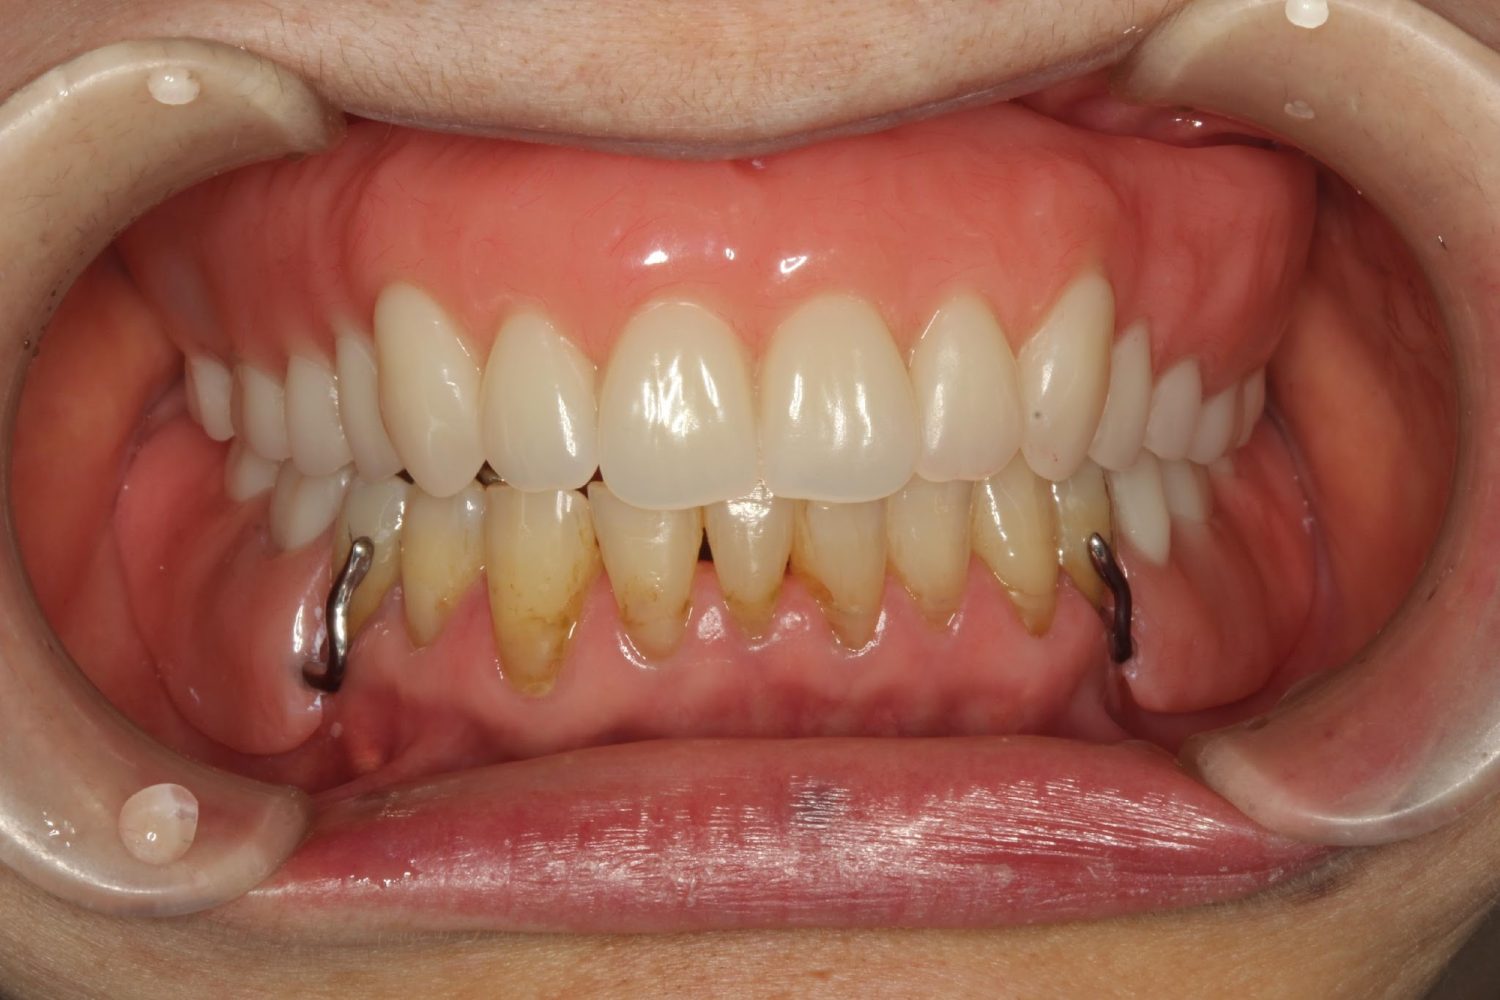

インプラント治療の症例紹介⑤

Before

After

主訴

歯肉腫脹、咬めるようにしたい

治療内容

重度歯周病により全ての残存歯保存不可能な状態。上下顎ボーンアンカードブリッジによる咬合再構成。

治療費

12,621,400円(税込)

治療期間

22ヶ月

通院回数

28回

想定されたリスク

※上部構造の形態が複雑になるため清掃が難しくなる、インプラント周囲炎の恐れがありました。

濱 仁隆先生

浜歯科

上顎8本下顎7本のインプラント体埋入によるボーンアンカードブリッジ。